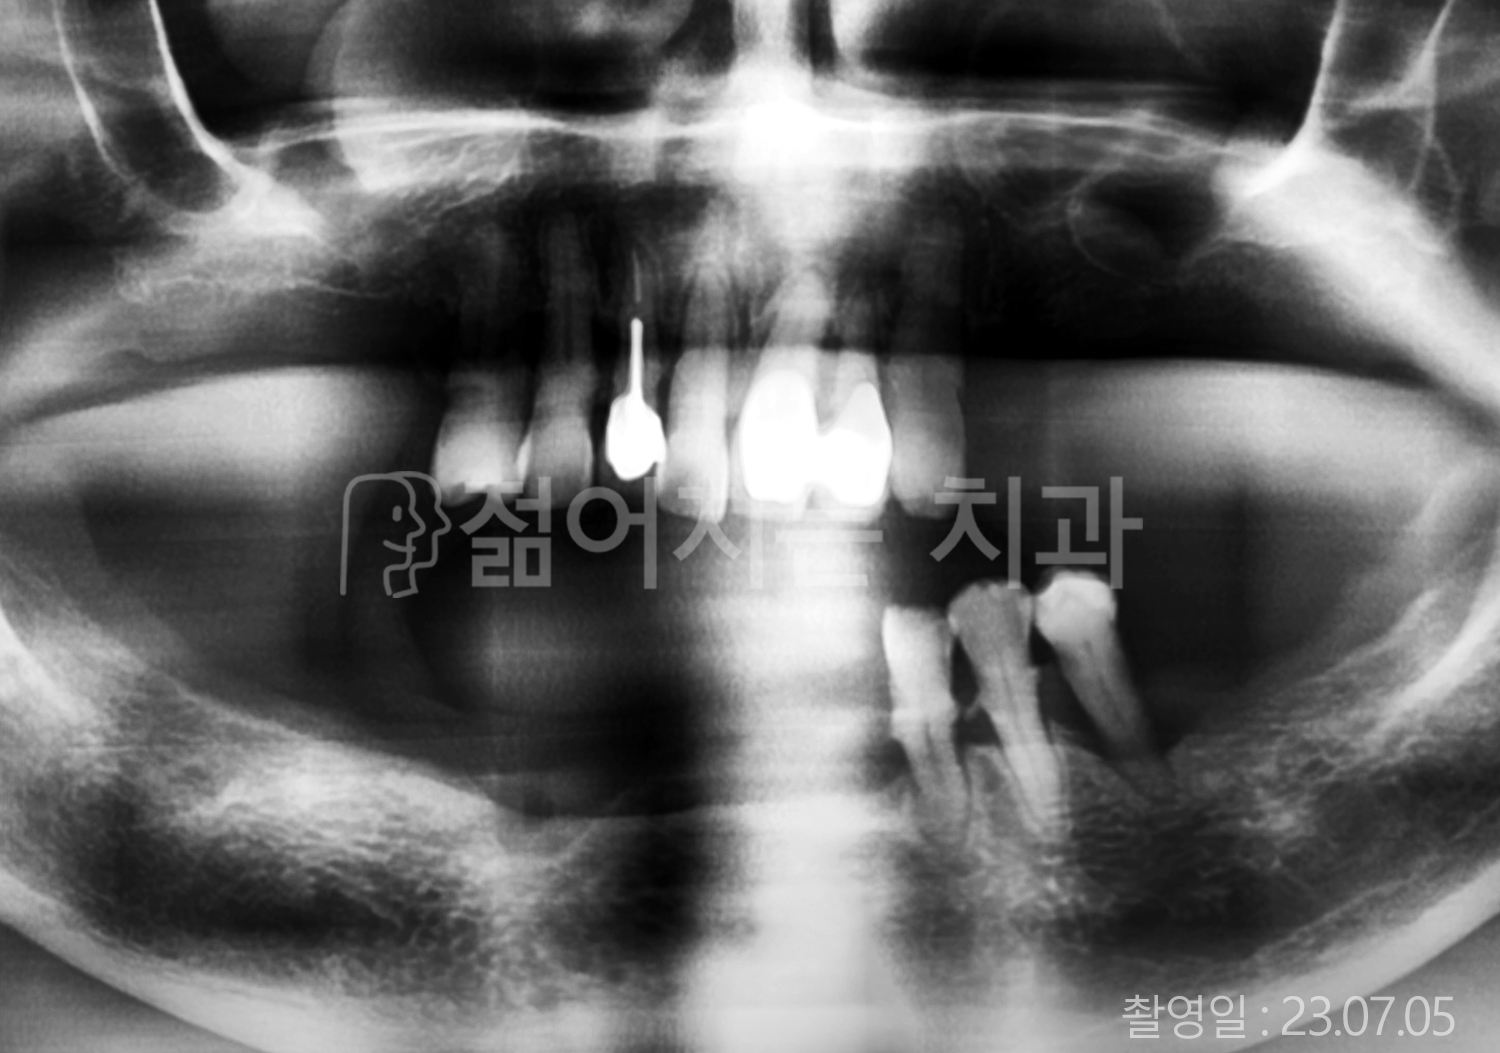

• 70대 전체치아 10개 이상 임플란트